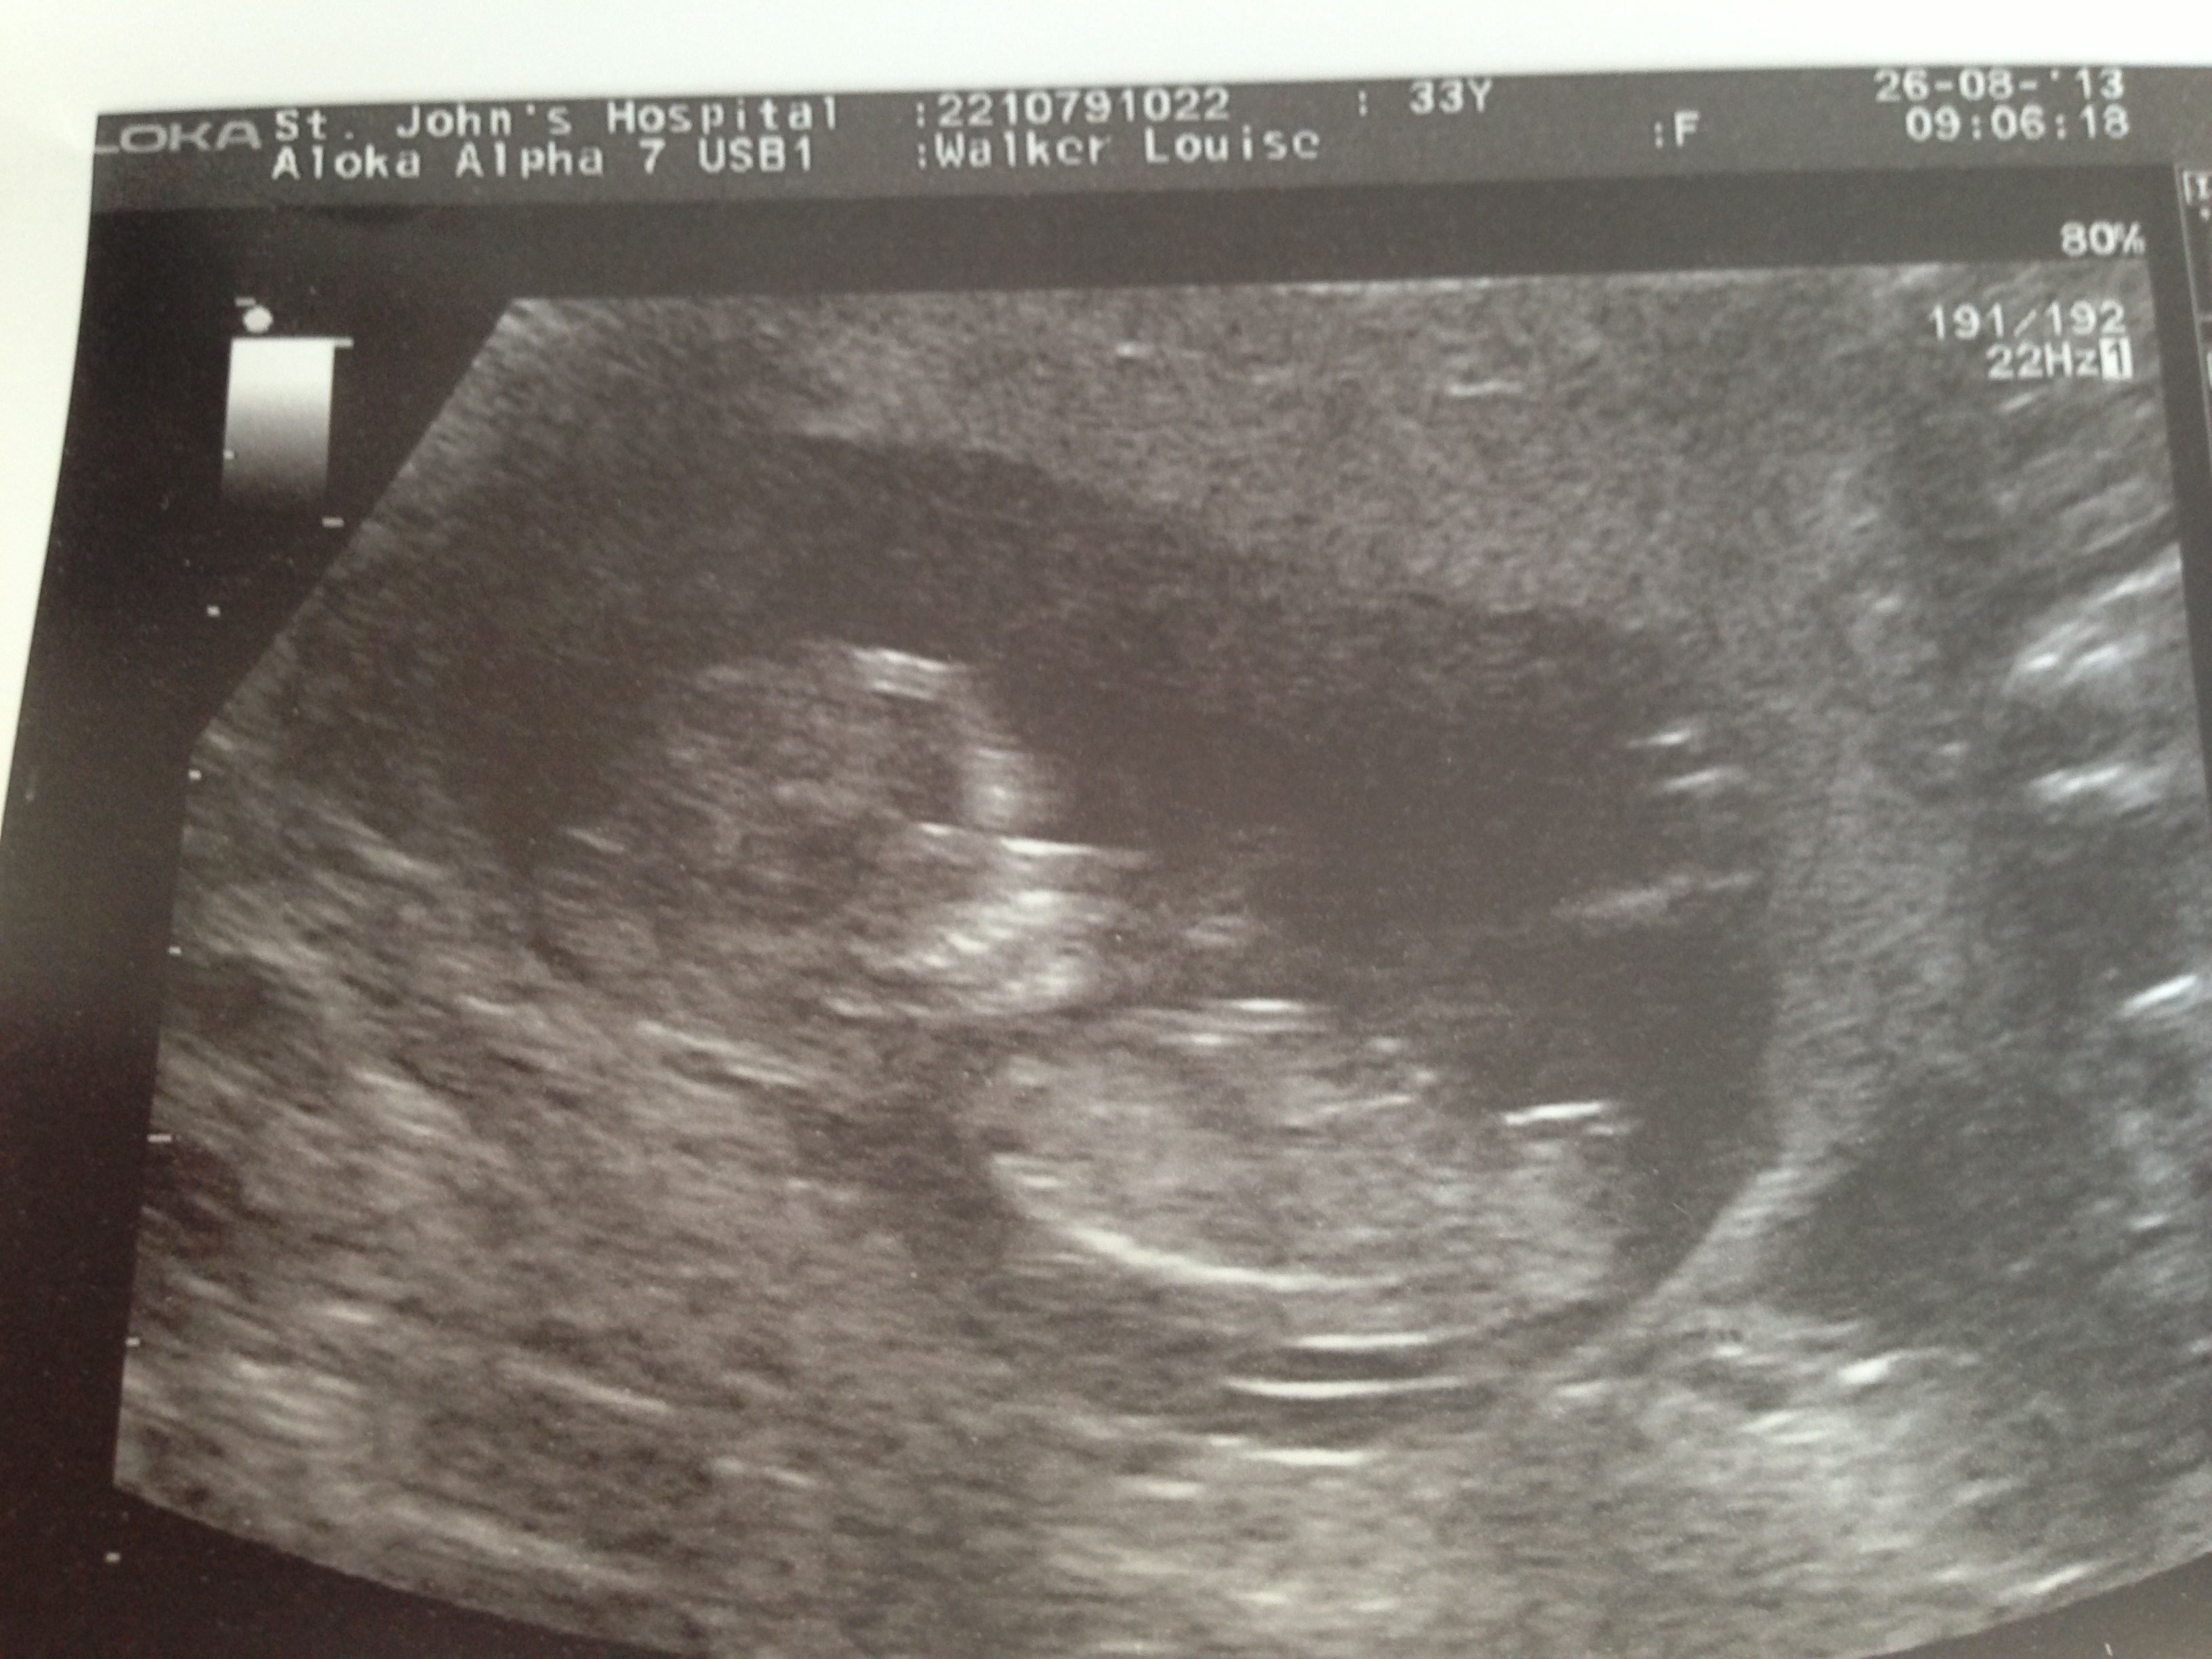

Maybe pink.

Thinking girl.

I would guess girl x

I would guess girl too x